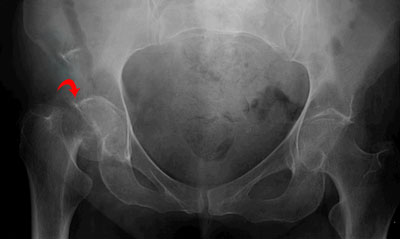

Clinical Significance of Hip Bone

There are 2 typical methods of fracturing the hip bone:

- Direct injury to the hip bone, for instance from an automobile crash.

- Forces transferred from the lower limb, for instance a heavy fall on the feet.

Hip Bone Fracture

Fractures frequently happen at the weaker points of the hip bone. These are the pubic rami, the acetabulum or around the sacroiliac joint. A common problem of hip bone fractures is soft tissue injury. Particularly, the bladder and urethra have high threat of damage.